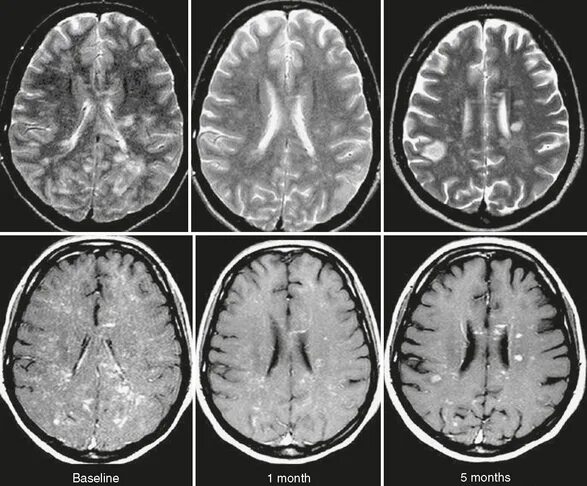

Марбуг